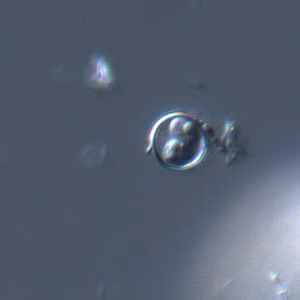

Cyclospora cayetanensis oocysts in wet mounts.

- Wet mounts (by conventional light microscopy, which can be enhanced by UV fluorescence microscopy or differential interference contrast [DIC, Nomarsky])